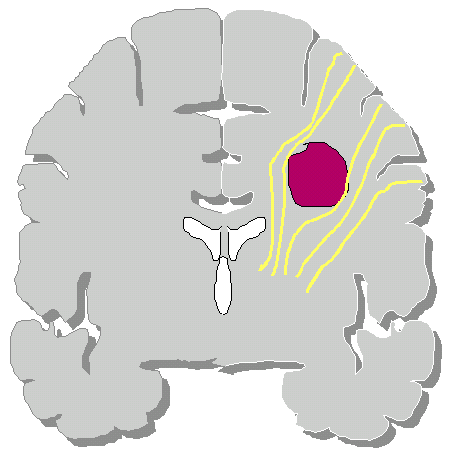

Un glioma può essere quindi distinto in tre tipi (Daumas-Duport): |

Tipo

I: lesione circoscritta |

II: lesione compatta ed area di tessuto cerebrale infiltrato |

III: lesione diffusa con parenchima infiltrato |

|

Grazie alla tecnologia attuale, una massa tumorale compatta, che sposta il tessuto cerebrale può essere asportata praticamente da qualsiasi sede. La parte infiltrante invece potrà essere asportata solamente se questa interessa aree non critiche altrimenti il rischio di danni è molto alto. Parlando però di gliomi, la componente infiltrante è quasi sempre presente.